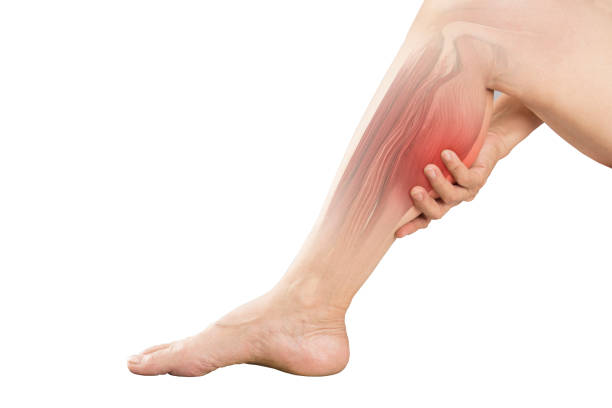

운동 방식

운동은 건강에 매우 중요한 요소이지만, 운동 중 근육에 지속적인 부담이 가해지면 혈액순환이 증가하고 산소와 영양분이 부족해져 다리에 피로감과 저림이 생길 수 있습니다.

특히 장시간에 걸쳐 반복적이거나 무리한 운동을 하면 다리에 저림이 생기기 쉬운데, 장거리 달리기는 근육과 인대에 지속적인 부담을 주기 때문에 다리 저림이 발생할 수 있고, 스쿼트나 런지 등 무릎과 다리 관절을 많이 사용하는 운동도 다리 저림을 유발할 수 있습니다.

과도한 운동은 오히려 건강에 해로울 수 있습니다. 운동 중 다리에 저림을 느낀다면 운동 강도를 줄이시고 천천히 운동 강도를 높이 시기 바랍니다. 또한 적절한 휴식을 취하고 꾸준히 스트레칭을 하여 근육을 이완시키는 것이 좋습니다.